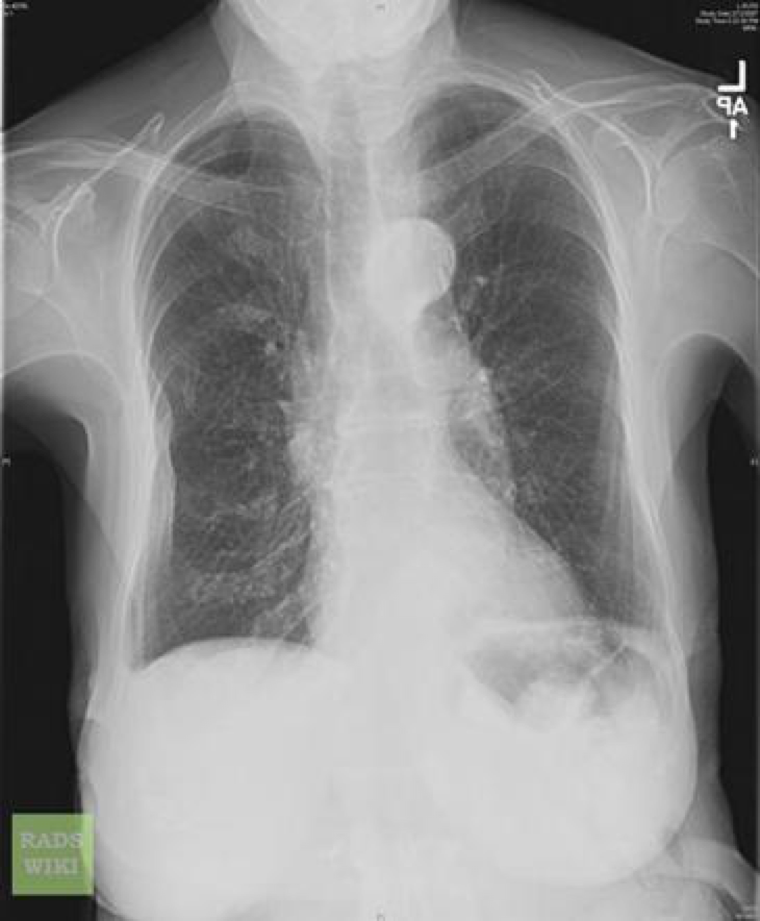

Plan: FBC, U&E, CK, CRP, CXR, catheterise and urine dip, IV meropenem, 0.9% saline 500 mls over 1 hr, CT head, admit to medicine. Hb 89, MCV 79, WCC 16.9, platelets 411, CK 2000, CRP 66, Urea 18.1, Cr 116, eGFR 40, CXR – cardiomegaly/patchy consolidation right base.

Chest X-ray